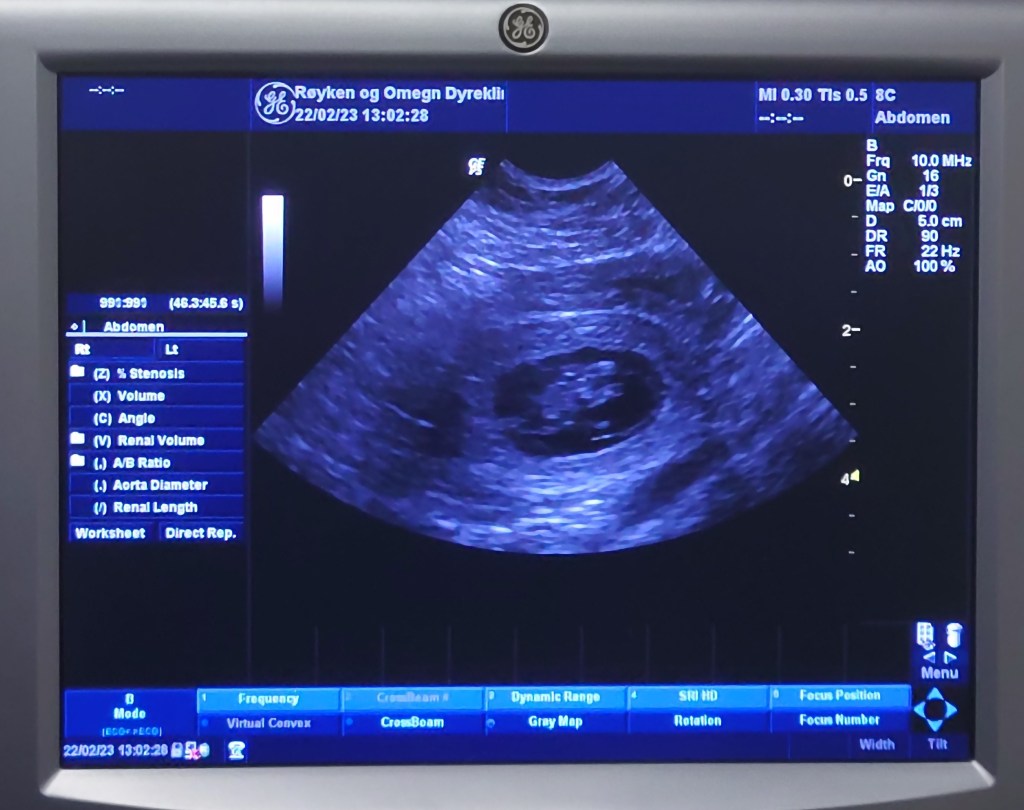

Vi så akkurat det vi hadde forventet å se; flere ‘bobler’ som akkurat var i ferd med å skifte form fra helt runde til avlange. Og vi kunne se at det var noe inni dem også. Det er vanskelig å se antall på ultralyd, men vi så hvertfall fire forskjellige og flere enn det. Det vil jo da si at alt er iorden. Hadde vi kun sett en – eller ingen, så kunne vi jo ikke være sikre på at det var OK.

Veterinæren sier at Quinny ser ut til å være helt i rute ift parringstidpunktet. Dvs forventet nedkomst ca 2. april. Jeg har bursdag 3.april og det ville jo være en fantastisk bursdagsgave!